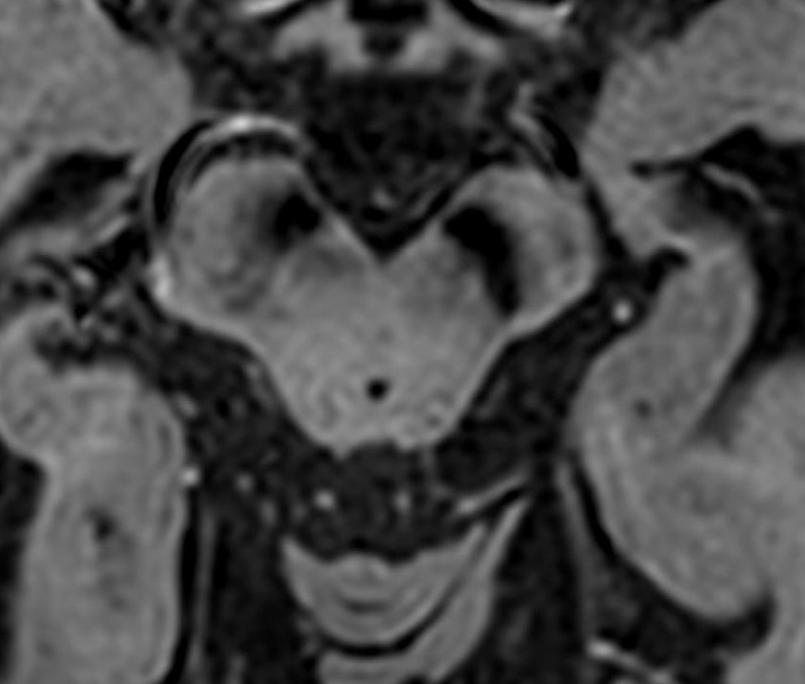

男性68岁,四肢末梢麻木2月余,伴有站立不稳,加重1周,不能独立行走。查体双侧跟膝胫试验欠稳准,双侧位置觉、震动觉减退。

答案:脊髓亚急性联合变性。患者老年男性,亚急性病程,以深感觉受累为主要表现,脊髓影像长节段病灶,轴位显示后索病灶“圆点征”,颅内影像改变无特异性,NMOSD相关抗体检测以及OB均阴性。其特征性影像有“圆点征”、“小字征”、“三角征”、“八字征”等。